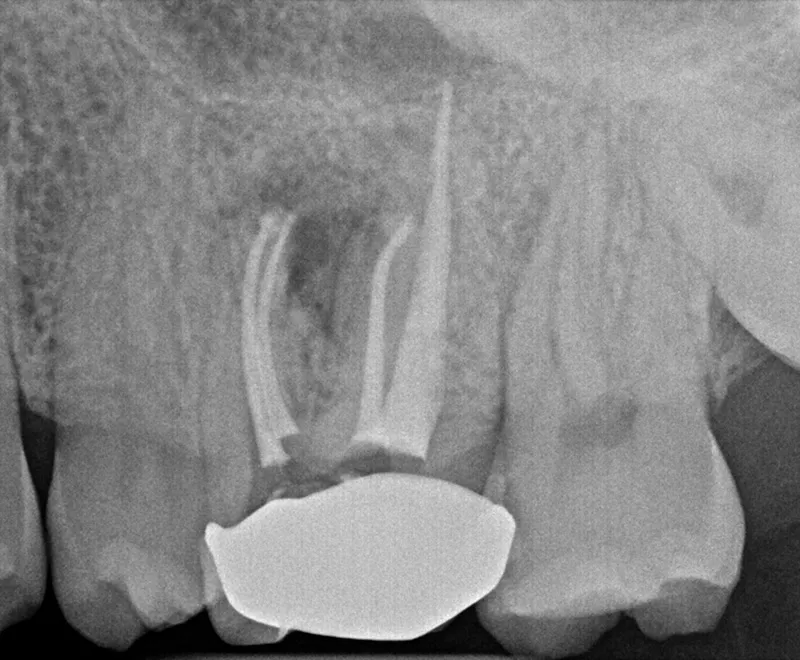

Image

Root canal retreatment after

After